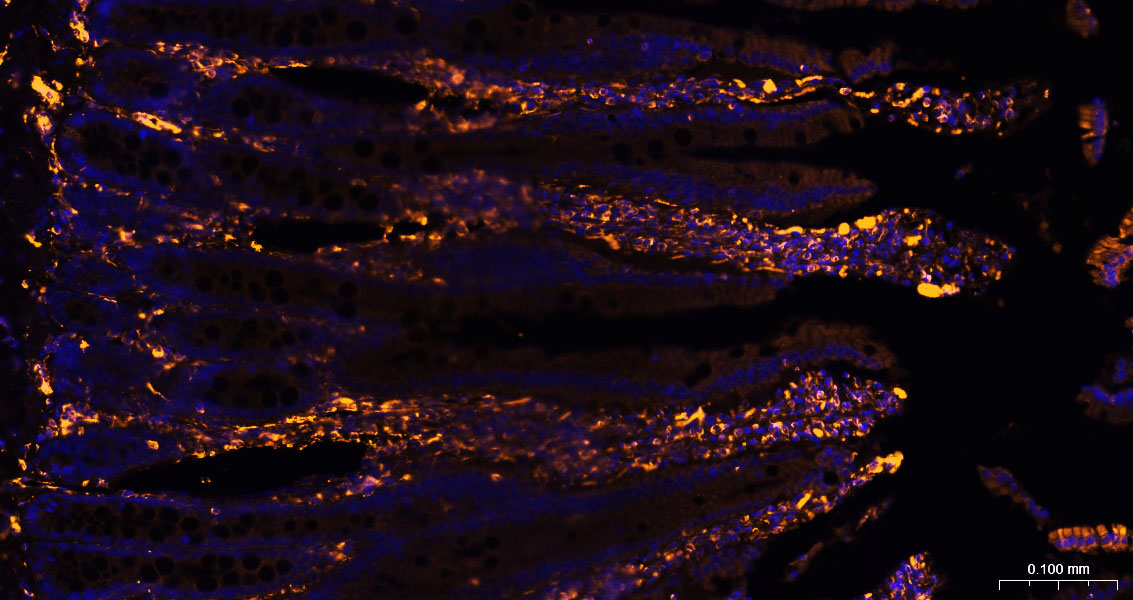

Paraformaldehyde-fixed, paraffin embedded Mouse Small Intestine ; Antigen retrieval by boiling in sodium citrate buffer (pH6.0) for 15min; The section was incubated with Vimentin Polyclonal Antibody, Unconjugated (bs-8533R) at 1:200 overnight at 4°C, followed by a conjugated Donkey Anti-Rabbit IgG antibody (bs-0295D-BF555) for 90 minutes, and DAPI for nuclei staining.

Paraformaldehyde-fixed, paraffin embedded Rat Small Intestine ; Antigen retrieval by boiling in sodium citrate buffer (pH6.0) for 15min; The section was incubated with Vimentin Polyclonal Antibody, Unconjugated (bs-8533R) at 1:200 overnight at 4°C, followed by a conjugated Donkey Anti-Rabbit IgG antibody (bs-0295D-BF555) for 90 minutes, and DAPI for nuclei staining.